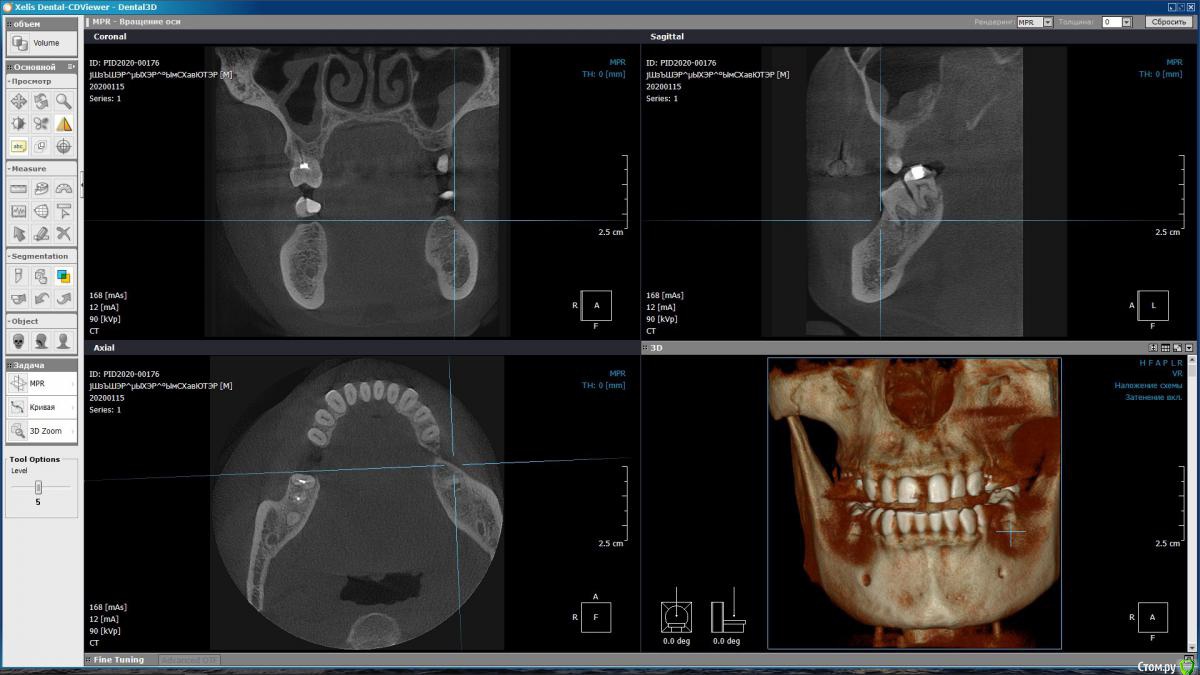

m-e-a Опубликовано 19 января, 2020 Автор Поделиться Опубликовано 19 января, 2020 (изменено) Сделала срезы как смогла, не умею я смотреть КТ Изменено 19 января, 2020 пользователем m-e-a Ссылка на комментарий

red_butler Опубликовано 19 января, 2020 Поделиться Опубликовано 19 января, 2020 На представленных срезах, показаний к удалению не увидел. Нужно смотреть очно и «крутить» Кт Ссылка на комментарий